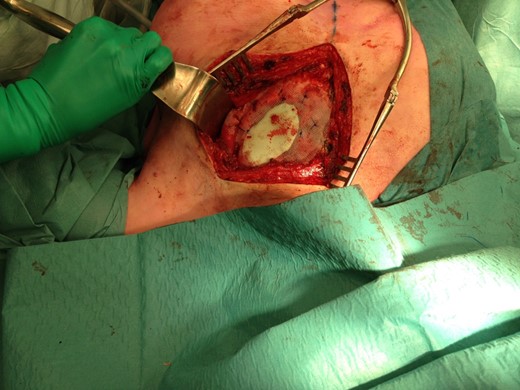

The size of the thoracic wall defect following resection measured 8 by 5.5 cm A patch was prepared using two polypropylene meshes and interpolate of methyl methacrylate (Fig. 3). The patch was placed and tightened to the periosteum using prolene sutures (Fig. 4). Figure 5 shows the resected tumour. Finally, subcutaneous tissue and skin were closed in layers using a Vicryl and intracutaneous Monocryl suture.

Preparation of the patch with two polypropylene meshes and interpolate of methyl methacrylate.